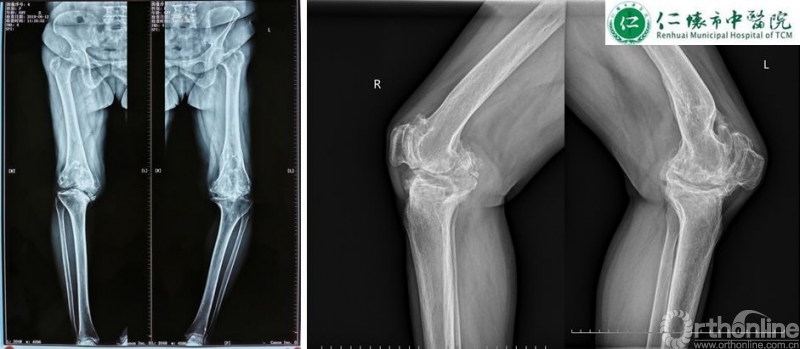

课程分享结束后,进入病例分享环节,四家与会医院分别展示各自病例并就术中存疑和李子剑教授探讨取经。仁怀市中医院分享了一例经典的使用ACCK假体复杂右膝关节置换手术:

术前影像: